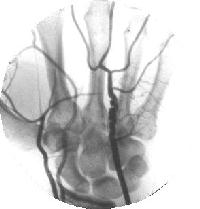

Clinical Example: Arteriogram of incomplete palmar arch and ulnar artery aneurysm

Arteriogram demonstrating both an incomplete palmar arch and an abnormality of the ulnar artery distal to the hook of the hamate. The patient had embolic ischemic problems and underwent excision and repair. Read by the radiologist as fibromuscular hyperplasia, by the pathologist as aneurysm.